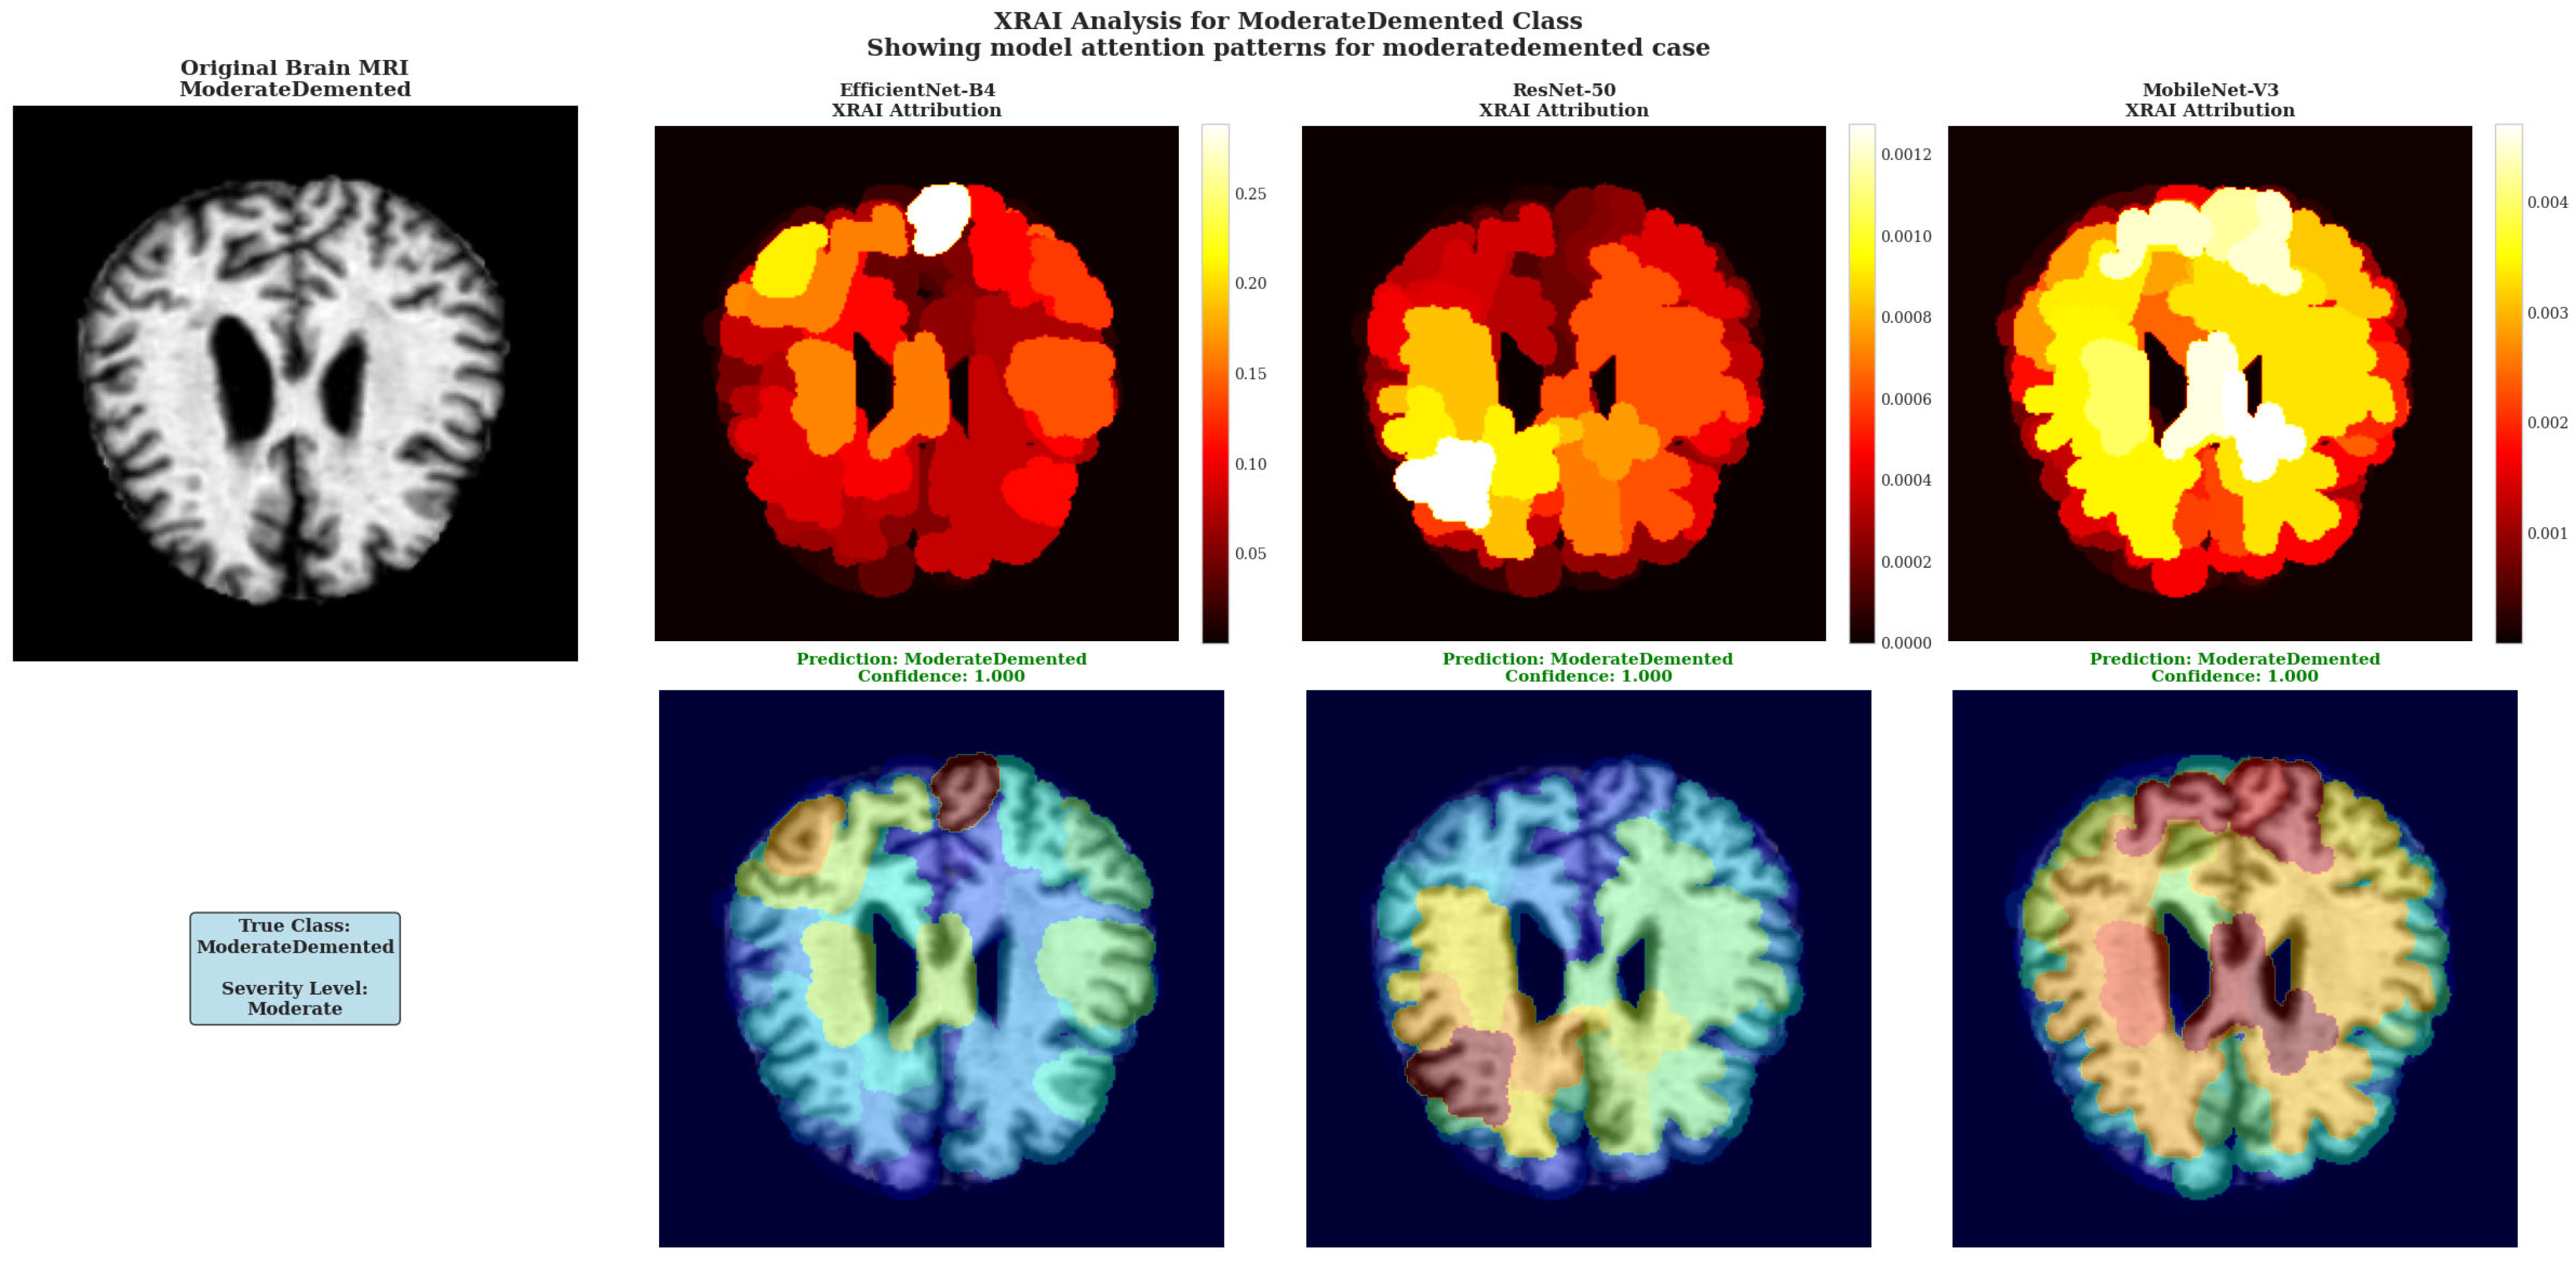

XRAI Analysis for ModerateDemented Class showing model attention patterns for moderate dementia case. All three architectures demonstrate heightened attribution intensity consistent with more pronounced pathological changes in moderate-stage dementia.

The ModerateDemented case revealed heightened model attention across all architectures, consistent with more pronounced pathological changes expected in moderate dementia stages (Figure 8). Each architecture demonstrated distinct attribution approaches with all models achieving perfect 1.000 confidence scores, indicating robust classification performance across different analytical methodologies.

EfficientNet-B4 showed concentrated attribution in specific cortical regions with peak intensities reaching 0.25–0.30 according to the color scale, displaying focused white regions indicating selective high-importance area detection. ResNet-50 demonstrated multiple discrete white and yellow regions distributed across cortical areas, maintaining attribution values around 0.0010–0.0012 with varied spatial coverage. MobileNet-V3 exhibited extensive high-attribution regions with large white and yellow areas and attribution values reaching 0.004 based on the color scale.

The architectural differences in attribution pattern generation demonstrate the diverse approaches these models employ for moderate dementia classification, with each showing distinct spatial distribution characteristics while maintaining equivalent classification accuracy. This diversity in attribution patterns provides complementary insights into model decision-making processes without favoring any single architectural approach.